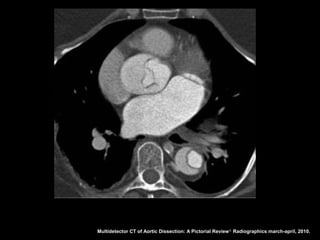

Dissecção aórtica

Angiotomografia

Diagnóstico: identificação do flap intimal, que se

apresenta como uma fina membrana separando a

luz falsa da verdadeira;

Sensibilidade e especifidade acima de 95% na

detecção do flap intimal;

Após diagnóstico: localizar, definir envolvimento de

ramos aórticos e identificar fatores agravantes

relacionados à própria aorta.

Multidetector CT of Aortic Dissection: A Pictorial Review 1. Radiographics march-april, 2010.